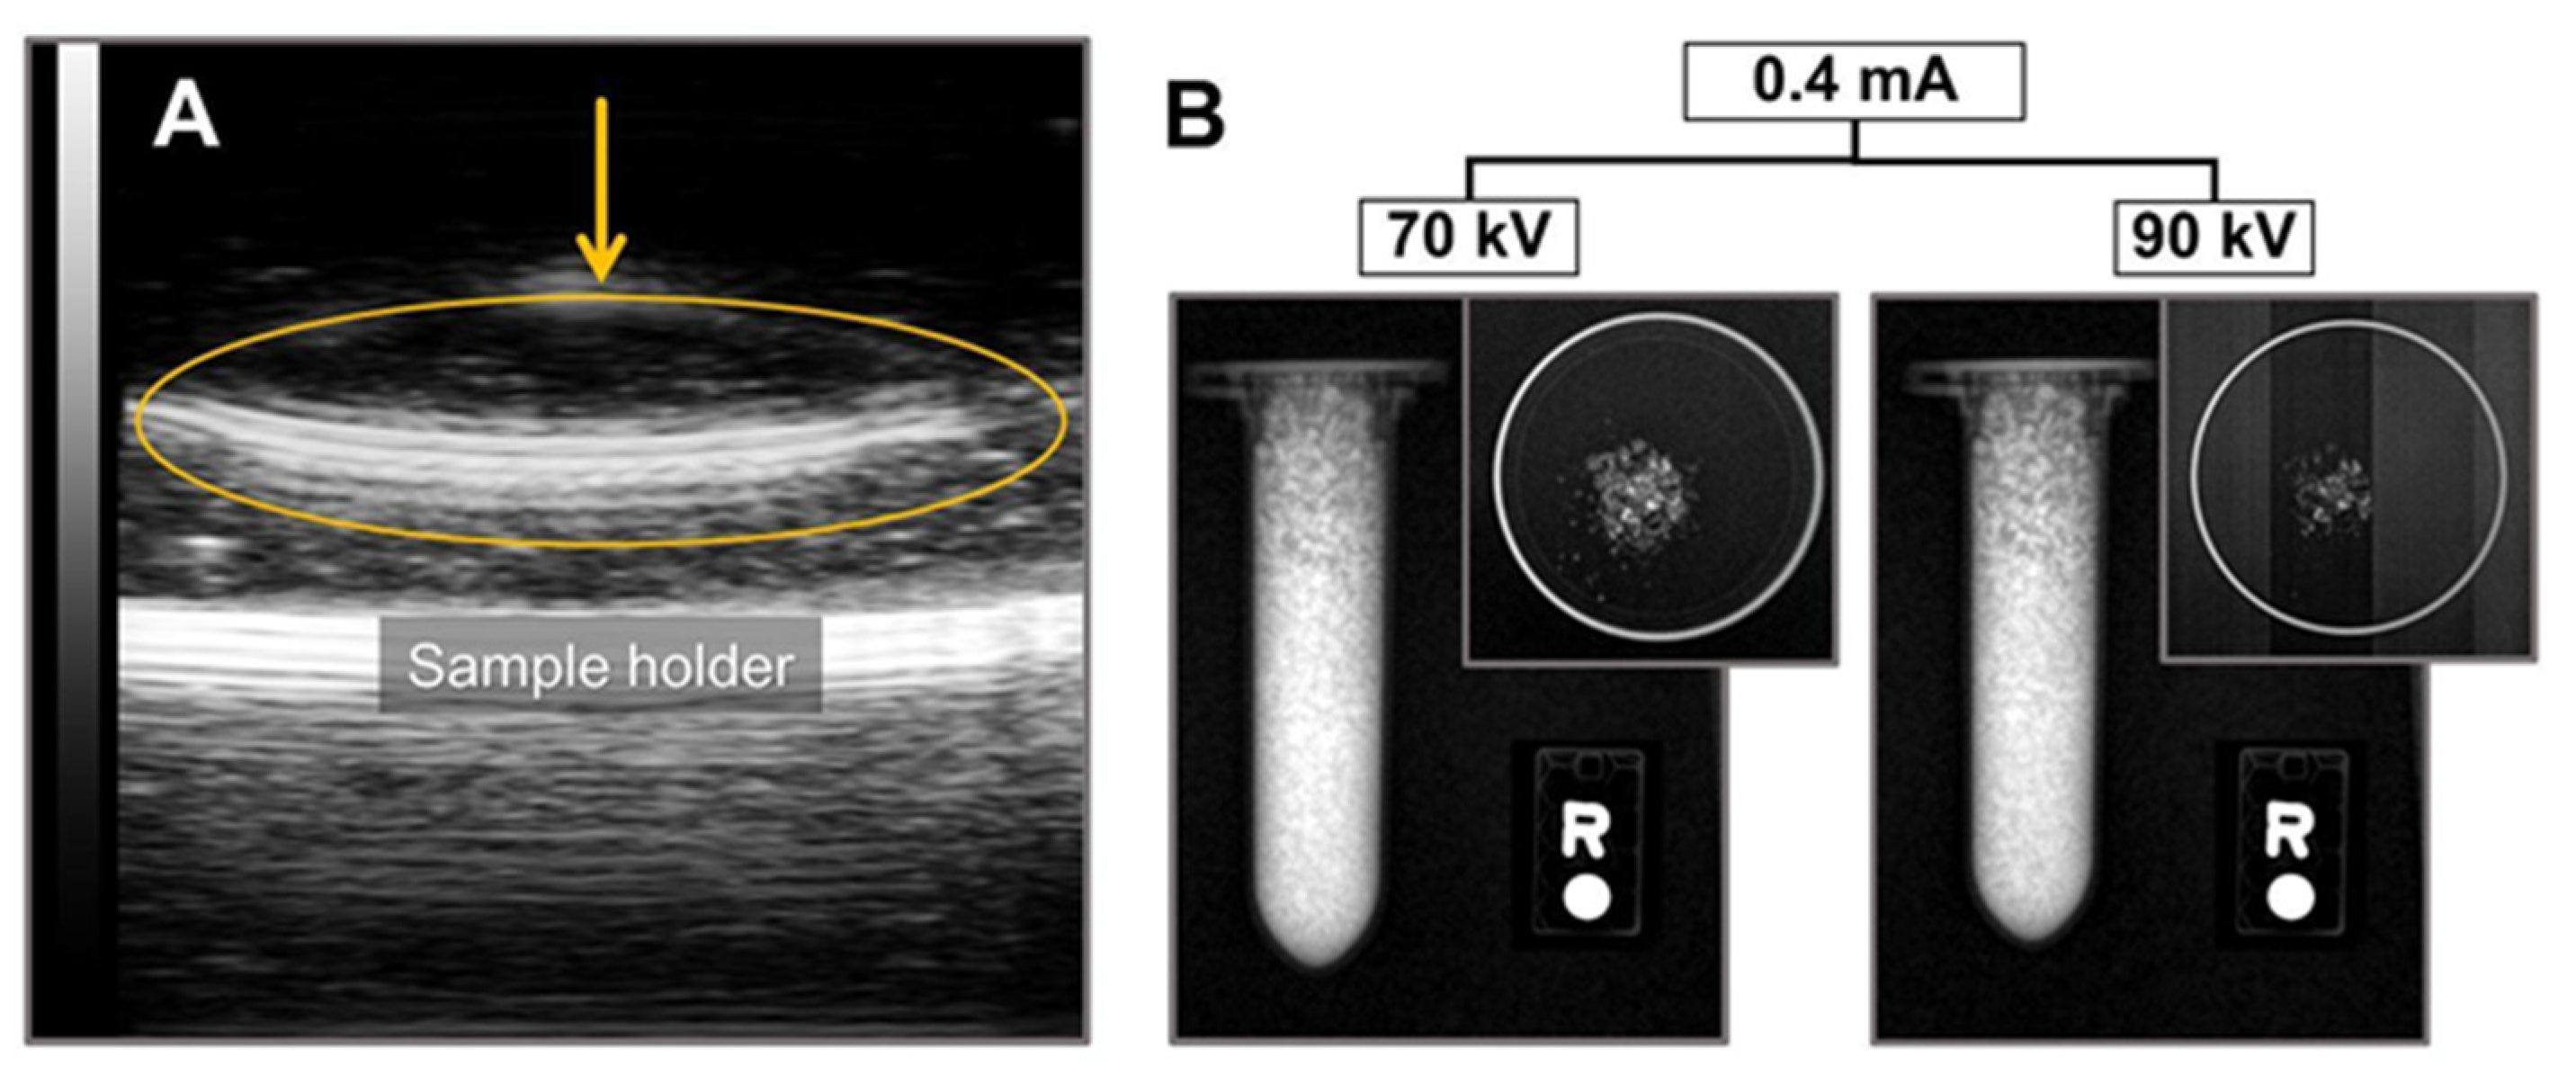

The ultrasound (US) imaging test, performed by subjecting an Eppendorf tube filled with part-CaF2 (Figure 7A) to US irradiation, demonstrated the US absorption properties of part-CaF2. In this image, part-CaF2 was suspended in water to reproduce a tissue environment (performed by casting the part-CaF2 into a flat petri dish), showing that US attenuation was exclusively generated by part-CaF2 reaching almost its maximum intensity. US attenuation occurs with sonosensitizers when the cavitation, followed by the collapse of small bubbles, produces enough energy to induce heating [6]. Although the mechanism of sonosensitizer excitation is not fully understood, most molecules exhibiting US attenuation contain halogen atoms in their structure [6], a common feature shared by commercially available US contrast agents [8], polytetrafluorethylene [11], and the part-CaF2 described in the present work. Thus, the results suggest that fluorine atoms from part-CaF2 likely contribute to the US absorption. However, the presence of halogen atoms in the molecular structure is not a requisite for US attenuation by a given material, as reported recently [44]. To the best of our knowledge, this is the first report showing the US imaging properties of part-CaF2 materials. These outstanding results may elicit interest in calcium fluoride for use in biomedical imaging applications.

Figure 7.

(A) Ultrasound imaging showing part-CaF2 suspended in water (orange arrow). (B) X-ray image showing a 2 mL Eppendorf tube filled with part-CaF2 and a top view of powder dispersed into a petri dish subjected to different potential and the same current intensity.

Additionally, part-CaF2 exhibits X-ray attenuation, which is supported by the contrast signal observed in Figure 7B. Indeed, part-CaF2 neatly attenuates X-rays of different energies (i.e., different potentials applied at the same intensity). Moreover, the same material was subjected to different parameters by tuning the tube current and potential without affecting X-ray attenuation. This result highlights the capability of part-CaF2 to absorb the incident electromagnetic radiation of high energy X-rays at different conditions without affecting the yield.

The X-ray attenuation by part-CaF2 powder was evaluated in Eppendorf tubes and Petri dishes using a small preclinical micro-CT scanner (1076 Skyscan, Kartuizersweg, Belgium). The experimental parameters were set as follows: X-ray: 70 kV, 90 kV, 0.4 mA, 1 mA; resolution: 35 mm; pitch: 0.4; aluminum filters: 0.5 and 632 ms.